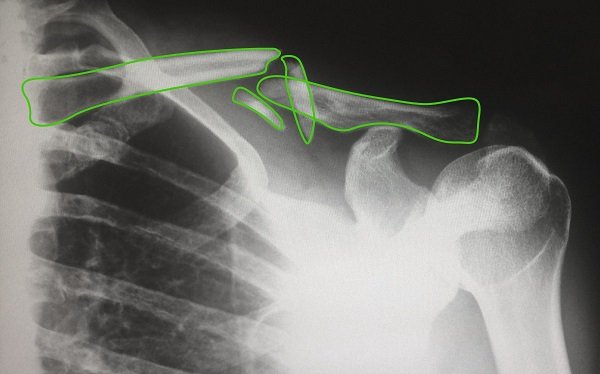

Medical image analysis

We create medical image analysis software for hospital and practices worldwide. In healthcare, computer vision is used as part of computer-aided diagnosis software helping doctors to detect abnormal signs in both 3D and plain images and videos. While not being able to replace human clinicians, computer vision applications can become their reliable assistants, pointing out areas worth special attention and thus reducing human error in radiology.

- CT

- MRI

- PET

- Ultrasound

- X-ray